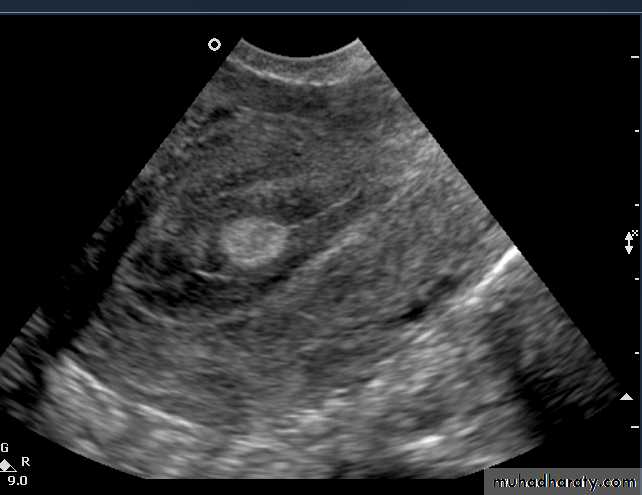

Endometrial adenocarcinoma.

(a) US image reveals a heterogeneous endometrial mass (arrows) that is difficult to distinguish from the myometrium. Cursors indicate the entire transverse width of the uterus.